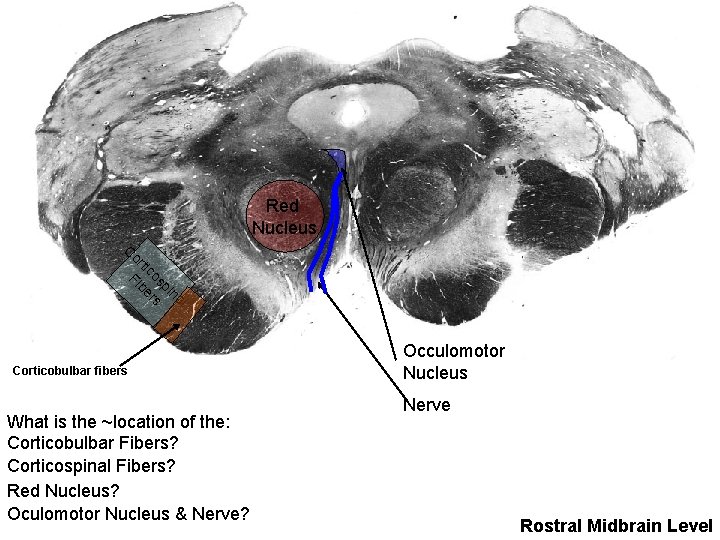

Red Nucleus C or tic Fi os be pi rs na l Corticobulbar fibers What is the ~location of the: Corticobulbar Fibers? Corticospinal Fibers? Red Nucleus? Oculomotor Nucleus & Nerve? Occulomotor Nucleus Nerve Rostral Midbrain Level